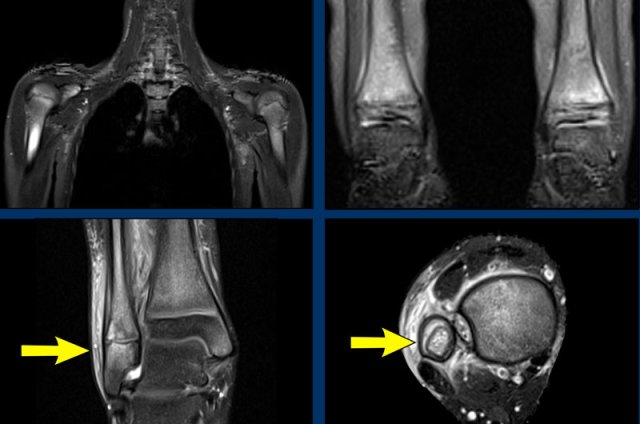

T2W series of a patient with amyloid arthropathy of the shoulder joint.

The findings are:

• Large intra-articular swelling caused by the deposition of hypointens amyloid.

• Spread to the subacromial and subscapular space.

• Large erosions of the humeral head.

This soft tissue swelling should not be mistaken for rice bodies as seen in rheumatoid arthritis.